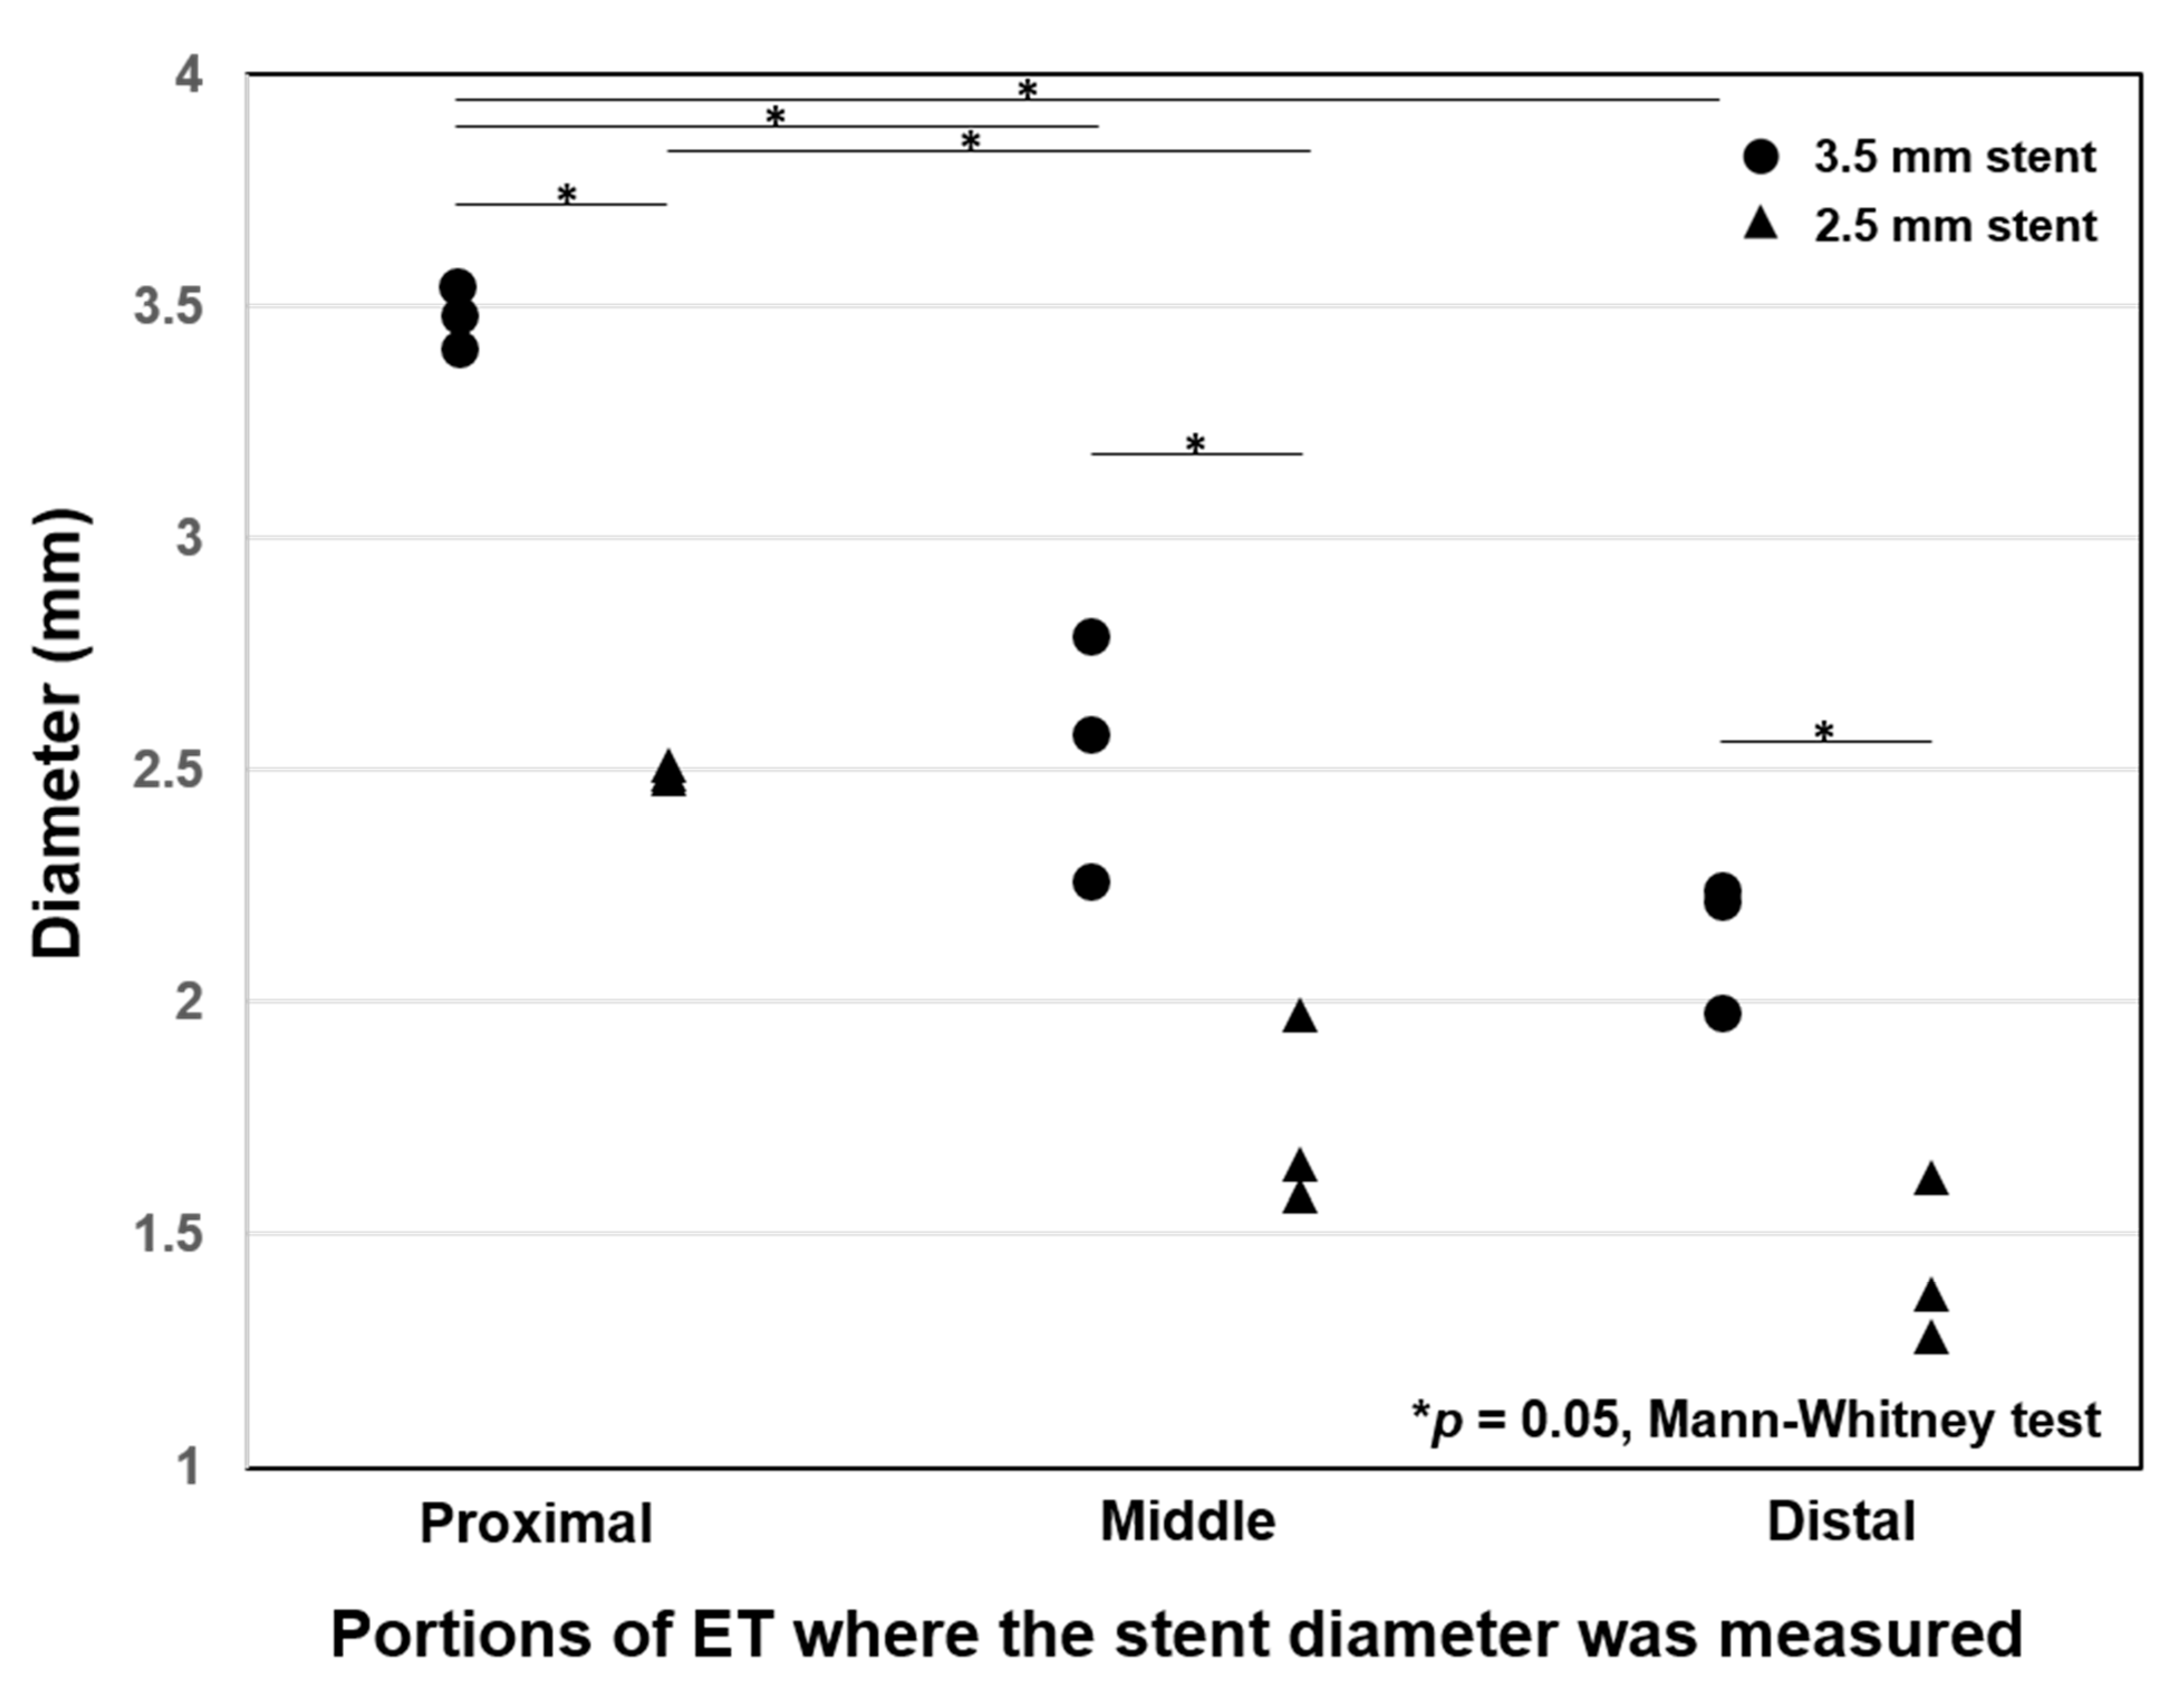

| Stent Diameter/Site | Location | Luminal Diameter (mm) | Decrease Rate (%) |

|---|---|---|---|

| 3.5 mm/Right ET | Proximal | 3.48 ± 0.06 | 0.9 ± 0.8 |

| Middle | 2.54 ± 0.17 | 27.4 ± 7.6 | |

| Distal | 2.15 ± 0.14 | 38.6 ± 4.1 | |

| 2.5 mm/Left ET | Proximal | 2.49 ± 0.04 | 0.4 ± 0.6 |

| Middle | 1.73 ± 0.21 | 30.8 ± 8.3 | |

| Distal | 1.42 ± 0.18 | 43.2 ± 7.1 |